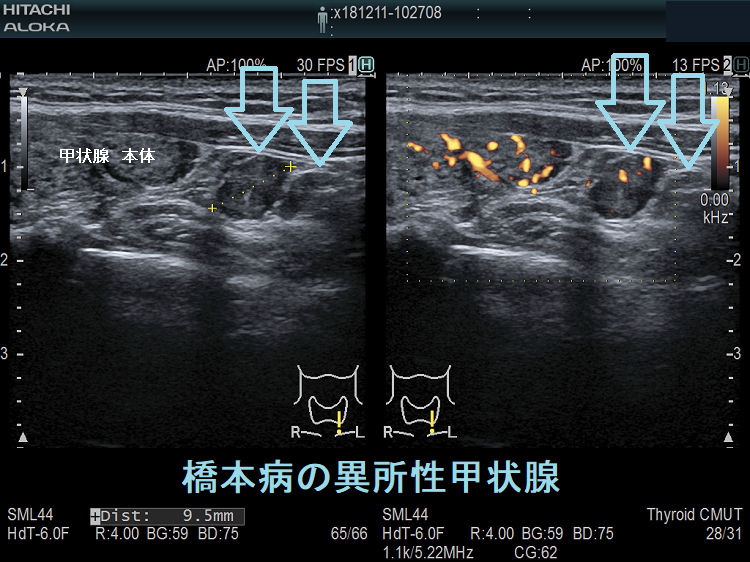

橋本病を合併し、副甲状腺と同じ位置にある頚部異所性甲状腺

橋本病の異所性甲状腺 超音波(エコー)画像

橋本病を合併し、下極の副甲状腺と同じ位置にある異所性甲状腺。甲状腺本体と同様の破壊性変化を認めます。

橋本病の異所性甲状腺 超音波(エコー)画像 ドプラーモード

橋本病を合併した頚部異所性甲状腺:下極の副甲状腺と同じ位置にある異所性甲状腺。特徴的な2連構造で、甲状腺本体と同様の破壊性変化を認めます。